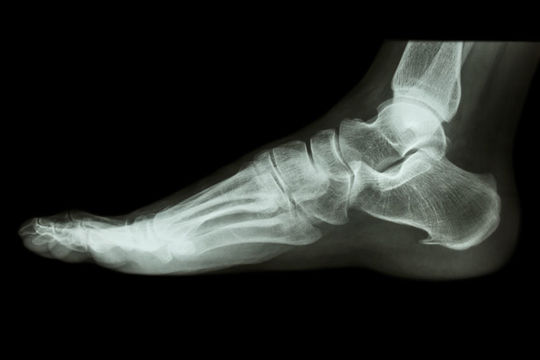

「このトゲが強い痛みの原因です」と整形外科の先生が言います。

そして、原因はトゲ(棘)では無いケースがよくあります。

かかとに小さな何かが写ったとしても、それは原因にはならず関係するかもしれない程度の事です(骨のヒビ、骨折などの外傷は別とします)